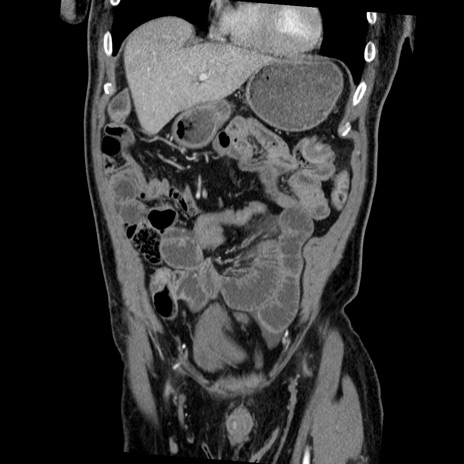

症例22(冠状断像)

【症例】50歳代男性

【主訴】腹痛

【現病歴】AVMからの被殻出血のため回復期リハ病棟入院中。 本日午後3時頃急に下腹部痛が出現した。

【既往歴】AVM、被殻出血、虫垂炎、高血圧

【身体所見】意識晴明、左半身不全麻痺、会話の理解は良好、36.5°C、腹部:膨隆、全体に板状硬、下腹部正中に圧痛点あり、反跳痛-、筋性防御不明、右下腹部にope scar

【データ】WBC 9400、CRP 0.06